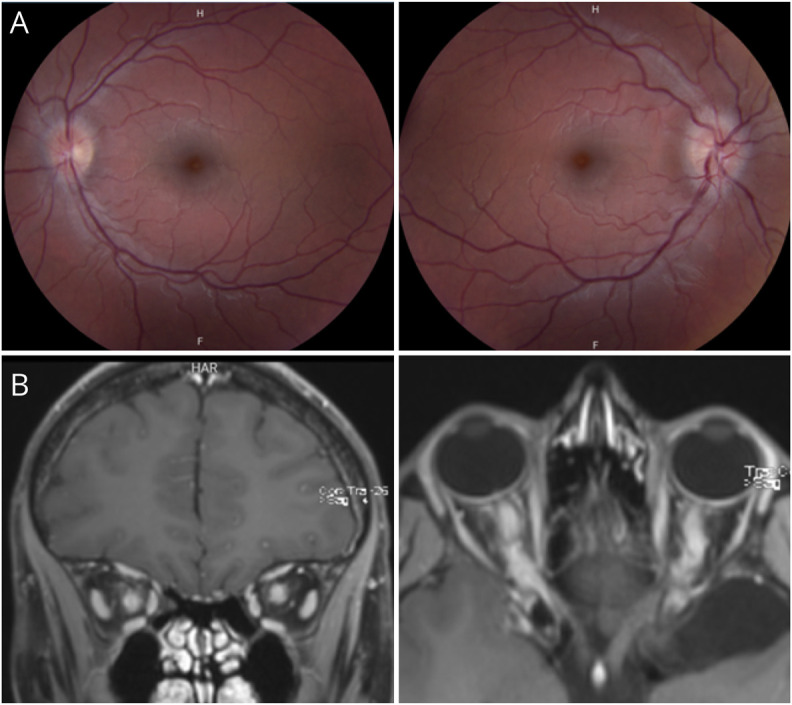

Results: In total, 8 of 350 (2.3%) MOGAD patients with ON experienced AF. Most patients (7/8, 87.5%) were women, and all reported periocular pain. Transient visual episodes were typically brief (median, 15 minutes; range, 1-300 minutes) and usually less than 1 hour (6/8, 75.0%). Amaurosis fugax affected the right (n = 4), left (n = 3), or both (n = 1) eyes. Within 1 week, 7 developed ON. MRI showed optic nerve enhancement in involved eye in 8 of 8 (100%). OCT completed in 1 patient at the time of AF showed increased peripapillary retinal nerve fiber layer thickness. No alternative diagnoses emerged during follow-up.